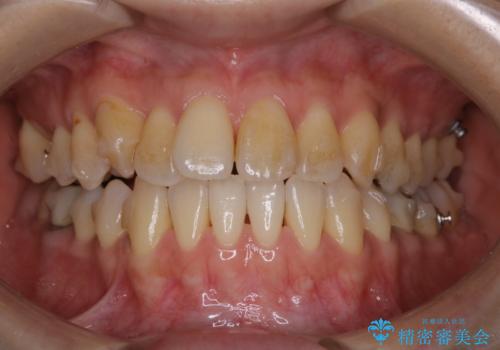

前歯が内側に入っている:インビザライン治療

- 上の前歯は内側に入っていることが気になりご相談にいらした方です。インビザラインにて治療を行いました。

1週間でのマウスピース交換を指示していましたが、20時間以上使えない時があると不安との事で、2週間ごとの交換にしていました(実際はほとんど20時間以上使用できていたようです)。治療終了まで時間はかかりましたが、最終的に綺麗に並べることができ、大変喜んでいただけました。